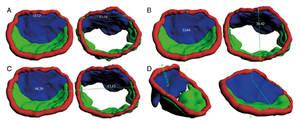

MRI with labeled structures from atlas registered to the CBCT. Registration was carried out with the open source imaging tool 3D Slicer, Version 4.4.0. |